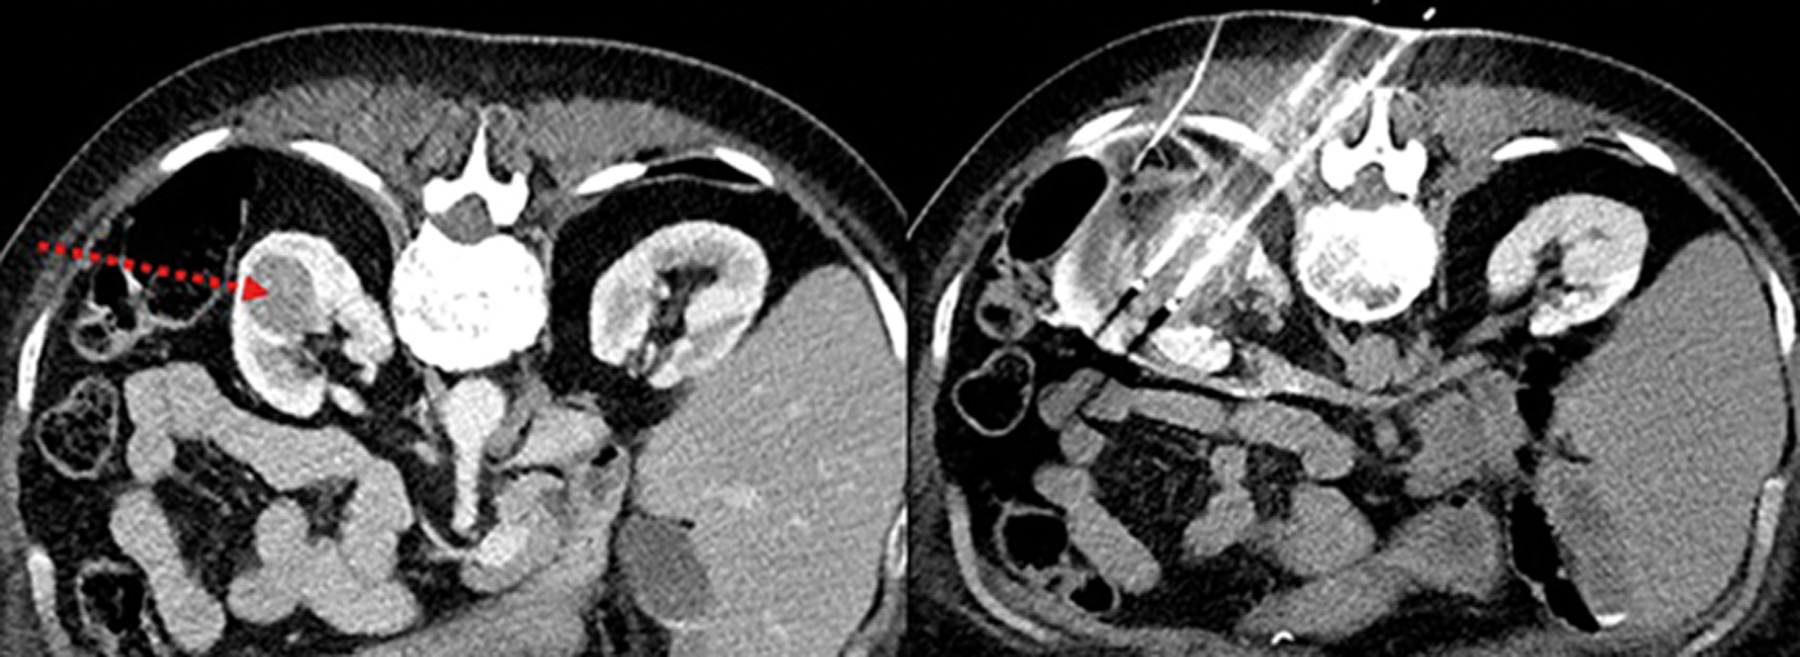

Case 3

A 77-year-old gentleman was diagnosed with the below 3cm renal lesion confirmed to be a renal cell carcinoma. Management options were discussed, and he opted for the below intervention.

Figure 4.

1. Can you describe the intervention shown in Figure 4?

2. Please outline the risks involved with this procedure.

1. This is cryoablation of a small renal tumour.

2. The complications involved with this procedure are listed below, along with their respective risks.